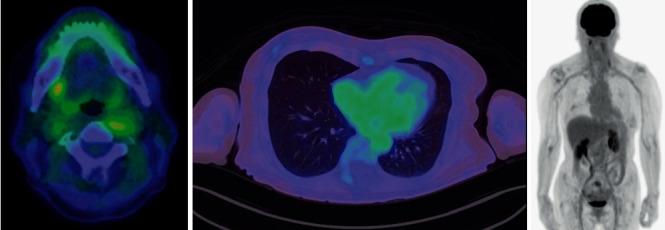

We report a case of amelanotic malignant melanoma (AMM) in a 66-year-old female. AMM of the lingual base was diagnosed based on a biopsy of late metastasis to the bone marrow of the L4 lumbar vertebra. The patient was initially treated with chemoradiotherapy after being misdiagnosed with poorly differentiated human papillomavirus- (HPV-) related squamous cell carcinoma of the oropharyngeal anterior wall. p16 immunostaining is used to diagnose HPV-related oropharyngeal cancer. However, while p16 expression is used as a surrogate marker of HPV infection, it is important to be aware that p16 protein overexpression can also be caused by other factors. Malignant melanoma is known to express the p16 protein. Morphologically differentiating between AMM and poorly differentiated squamous cell carcinoma based on hematoxylin-eosin staining is difficult. Therefore, in cases that are pathologically diagnosed as p16-positive poorly differentiated oropharyngeal squamous cell carcinoma, it is important to rule out AMM.

我们报告一例66岁女性的无色素性恶性黑色素瘤(AMM)。舌根部AMM是根据L4腰椎骨髓晚期转移的活检确诊的。该患者最初被误诊为口咽前壁低分化人乳头瘤病毒(HPV)相关鳞状细胞癌,之后接受了放化疗。p16免疫染色用于诊断HPV相关的口咽癌。然而,虽然p16表达被用作HPV感染的替代标志物,但必须注意p16蛋白过表达也可能由其他因素引起。已知恶性黑色素瘤会表达p16蛋白。基于苏木精-伊红染色在形态学上区分AMM和低分化鳞状细胞癌很困难。因此,在病理诊断为p16阳性的低分化口咽鳞状细胞癌的病例中,排除AMM很重要。